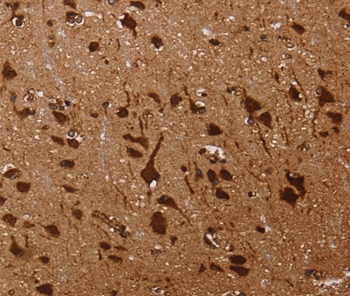

Immunohistochemical analysis of paraffin-embedded Human brain tissue using #36565 at dilution 1/60.